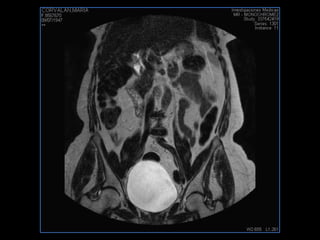

PROTOCOLO pelvis SAG T2, Y FAT SAT (FINOS) AXIAL T1  AX FAT SAT CON   GADOLINIO :  AX T1 Y COR T1 SAT: NO  FASE: RL THK: 3MM  COIL:  GAP: (FACTOR 1.4) 1MM FOV: 40 CM NEX:2 SINCRONIZACION RESPIRATORIA EN 3 O 4 CICLOS ALE